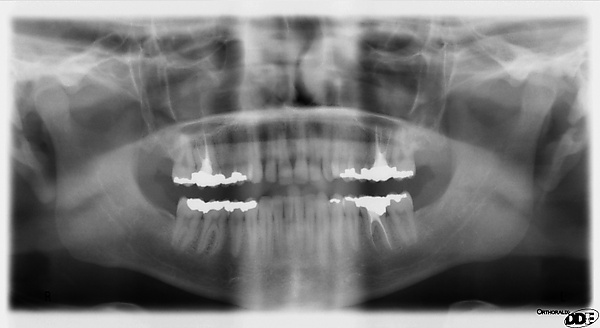

Ортопантомография (от греч.: orthos — прямой, правильный, pan — всё, tomos — ломоть, отрезанный кусок и grapho — писать, рисовать) — особый вид рентгеновской съёмки костей лицевого скелета, при котором они «развёртываются» в одну плоскость[1]. Другими словами рентгенологическое исследование в стоматологии, челюстно-лицевой хирургии, косметологии, позволяющее получать развёрнутое изображение всех зубов с челюстями, прилежащими отделами лицевого скелета. Является первичным рентгенологическим исследованием[2].

5. Контроль этапов лечения и динамики течения заболеваний (качество пломбировки канала, штифты, имплантаты и пр.).

Галерея